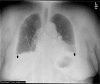

Lung ultrasound (LUS) is a dynamic, real-time, non-invasive bedside tool that offers increased sensitivity over standard imaging modalities in identifying pulmonary edema. This case highlights acute post-operative hypoxia secondary to pulmonary edema that was initially missed by chest radiography (CXR) and chest computed tomography (CT). The edema was diagnosed first on same day by bedside LUS, later seen on next day follow-up CXR and resolved with diuresis. LUS has demonstrated superior accuracy compared to CXR, but scant evidence compares it to CT. This case presentation serves to increase awareness of LUS as a highly sensitive and easy-to-use diagnostic tool for hospital providers in the evaluation of acute hypoxia.